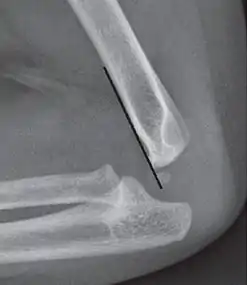

Anterior humeral line - It is a line drawn down along the front of the humerus on the lateral view and it should pass through the middle third of the capitulum of the humerus.[9] If it passes through the anterior third of the capitulum, it indicates the posterior displacement of distal fragment.[8]

Anterior humeral line (black line), with normal area passed on the capitulum of the humerus colored in green in a 4 year old child.[9]

The anterior humeral line is not reliable in children with sparse ossification of the capitulum, such as in this 6 months old child.[9]